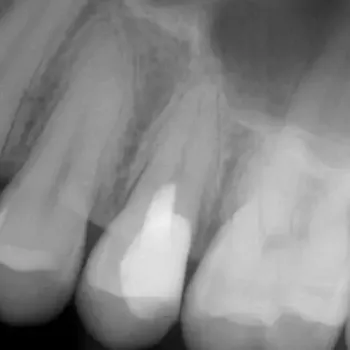

Fall 1: Revisionsbehandlung

Ausgangssituation